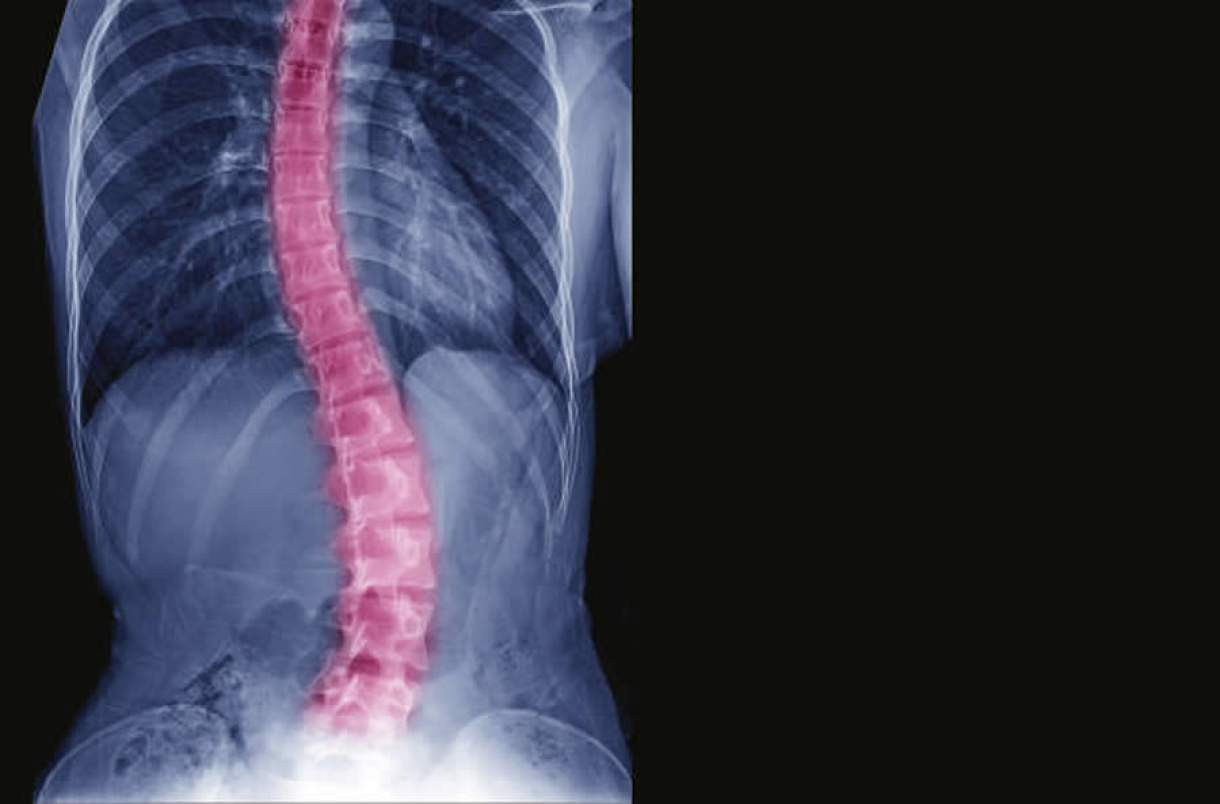

“A Escoliose Idiopática Adolescente (EIA) é uma curvatura anormal da coluna para um dos lados do tronco, trata-se de um desvio de coluna progressivo que pode ou não ser acompanhado de rotação das vértebras. Em 80% dos casos, as causas são desconhecidas e, por isso, ela é descrita como escoliose idiopática”, alerta Dr. Álynson Larocca Kulcheski, médico ortopedista do Hospital VITA, especialista em coluna.

Segundo o ortopedista, é a deformidade mais frequente da coluna. A coluna adquire um desvio das curvas naturais, que pode desencadear um desequilíbrio funcional. O desvio mais frequentemente observado é no plano frontal (visto de frente ou de costas) e nota-se uma inclinação da coluna para um dos lados.